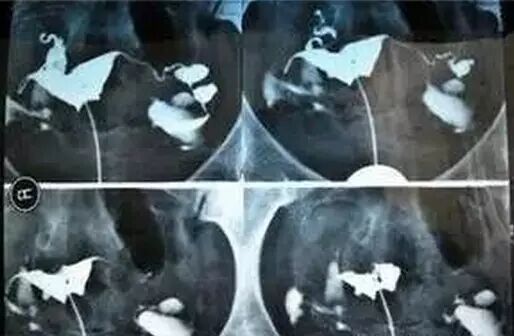

检查:依靠造影检查输卵管  安全高效副作用小

“在导致输卵管堵塞或通而不畅的原因中,80%左右与炎症有关。”张主任说,她接诊过一位35岁的盆腔炎患者,生育过一个小孩,二胎政策放宽以来,一直想再要个,可是一直没有怀上。她给这位患者做了孕前筛查,发现患者的子宫和卵巢均没有问题。考虑到盆腔炎症随着婚后生活时间的增长,发病率会增高,于是张主任又建议这位患者做了输卵管造影,结果显示她的输卵管有慢性炎症。【东方不孕专家解析】:不孕“瞄上”二胎妈 中年夫妻备孕到底有多难?-怀孕期

“输卵管通液是不孕症患者最基本的检查,由于其操作的盲目性和对操作人员要求熟练度极高,易导致误诊。”张主任说,目前输卵管盲目通液检查已经被淘汰,传统放射科开展的造影技术,可以通过显影监测。东方妇产医院临床上,这项技术对操作人员的专业经验提出挑战,只有操作经验丰富、有责任心的医生才能将此项技术产生的负作用降至最低,可以令患者快速吸收的造影剂,对身体副作用小,能够快速诊断输卵管堵塞及畸形位置,明确输卵管走形,且不影响以后的试孕。